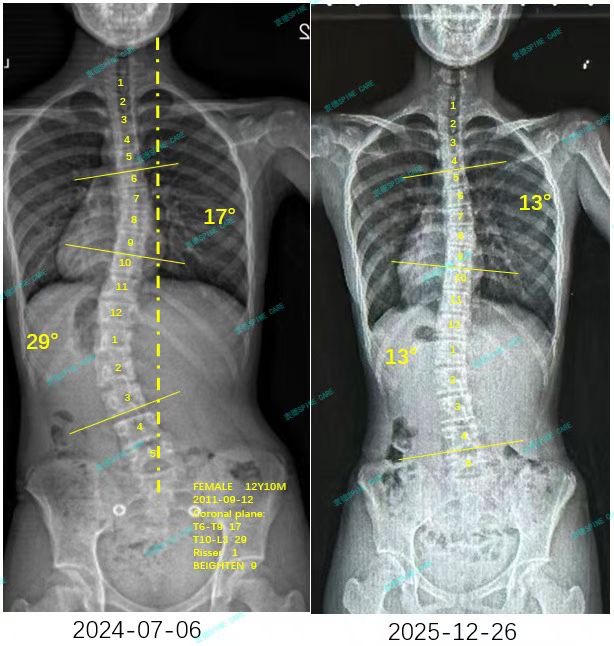

来自家长对衷德的评价(涵涵妈妈)

衷德脊柱,我们只关注侧弯保守治疗~

Zhongde Spine, bending no breaking ~